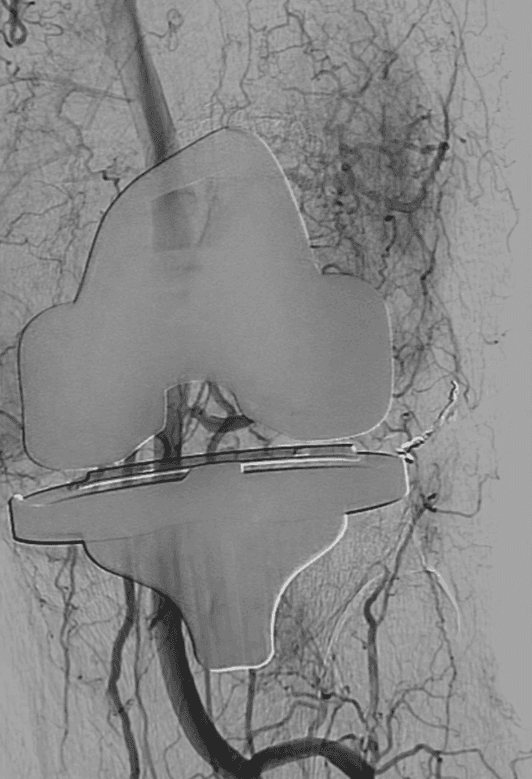

Embolization is a procedure in which the blood supply to a specific area is blocked. Hemarthrosishemarthrosis geniculate artery embolization treatment specialist embolization addresses the root cause of the problem, i.e., it blocks the abnormal arteries causing the bleeding into the knee joint.

Oftentimes, the culprits are the geniculate arteries that extend out into the knee joint and cause intermittent bleeding. Embolization of the geniculate arteries is a safe and effective treatment for recurrent spontaneous hemarthrosis after total knee replacement.

When someone has recurrent hemarthrosis after total knee replacement (bleeding continues to occur despite three or more joint aspirations), embolization offers a definitive solution. The exact source of bleeding is confirmed with angiography (imaging) and the bleeding artery is blocked with embolization. Compared with open surgery, embolization can be performed under local anesthesia, lowers the risk of infection, and expedites postoperative recovery.

Geniculate artery embolization is an outpatient non-surgical procedure with minimal downtime. The procedure is done in an outpatient state-of-the-art center where our interventional radiologist performs the treatment through a tiny tube called a catheter. This procedure can be performed by placing the catheter in an artery at the top of the leg (called a femoral approach).

The patient is given a local and topical anesthetic to numb the skin and a mild sedative so that the procedure is not painful. A sophisticated X-ray machine that creates moving pictures in “real” time enables the doctor to see the catheter as it is guided through the blood vessels and into the geniculate artery.

The final step in geniculate artery embolization is the injection of tiny particles the size of sand particles through the catheter. The particles lodge in the blood vessels bleeding into the joint and cutting off their blood supply.